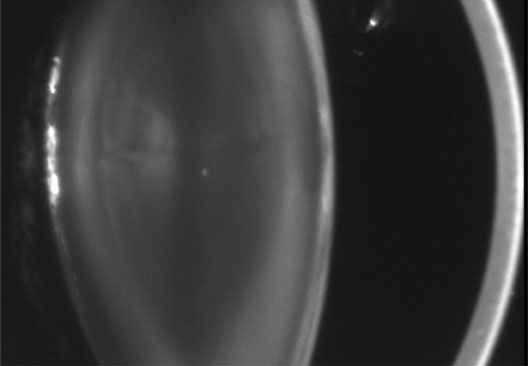

The dense bilateral lens opacities may present as a biconvex-shaped cataract or as posterior, polar, nuclear, or total cataract. The discoid lens shape may result from loss of lens material due to a posterior lens capsule defect4 or defective lens fiber formation and subsequent degeneration.5 The cataracts are present at birth, and glaucoma may be present congenitally or develop within the first 3 years of life. Other ocular findings may include corneal opacity, mitotic pupil, enophthalmos, and hypotonia.6 The cognitive impairment presents with a discrete behavioral phenotype that includes temper tantrums, irritability, complex repetitive behaviors, and unusual mannerisms. Severe renal Fanconi's syndrome may lead to progressive renal impairment. Most boys will develop a distinctive facies and habitus, and attain a height of less than 5 feet because of developmental retardation. Female carriers manifest characteristic but usually asymptomatic lenticular opacities that will correctly identify carrier status with 100% sensitivity in postpubertal females. These opacities are typically small, irregularly shaped, off-white or gray in color, nonrefractile in appearance, and distributed around the lens equator, more anteriorly than posteriorly (Figs. 1 and 2). Most importantly, and distinctively, these opacities are clustered in radial bands or wedges in the peripheral cortex of the lens and are visible by retroillumination. Typically, the opacities are moderately dense for one or two clock-hours, are then less numerous or even absent for another clock-hour or two, and so on. These opacities must be differentiated from the polychromatic, iridescent “crystals” found in Steinert's myotonic dystrophy (DM), gray-white random opacities in carriers of X-linked adrenoleukodystrophy, sutural opacities in Nance-Horan's (NH) syndrome, snowflake granules beneath the anterior and posterior capsule in diabetes mellitus, highly uniform white dots of hypoparathyroidism, and equatorial opacities in cataracta coronaria or ceruleana. Some females also manifest a dense white, central, posterior cortical cataract in the precapsular area. Although the posterior central cataract is apparently congenital, the equatorial and anterior cortical punctate opacities are uncommon in prepubertal female Lowe's syndrome carriers.7 Carrier status may also be confirmed by DNA diagnosis.

Fig. 2. OCRL. Retroillumination of small, irregularly shaped, nonrefractile anterior cortical opacities in the lens of a female carrier of OCRL. (Courtesy of Dr. R.A. Lewis, Baylor College, Houston, Texas.)